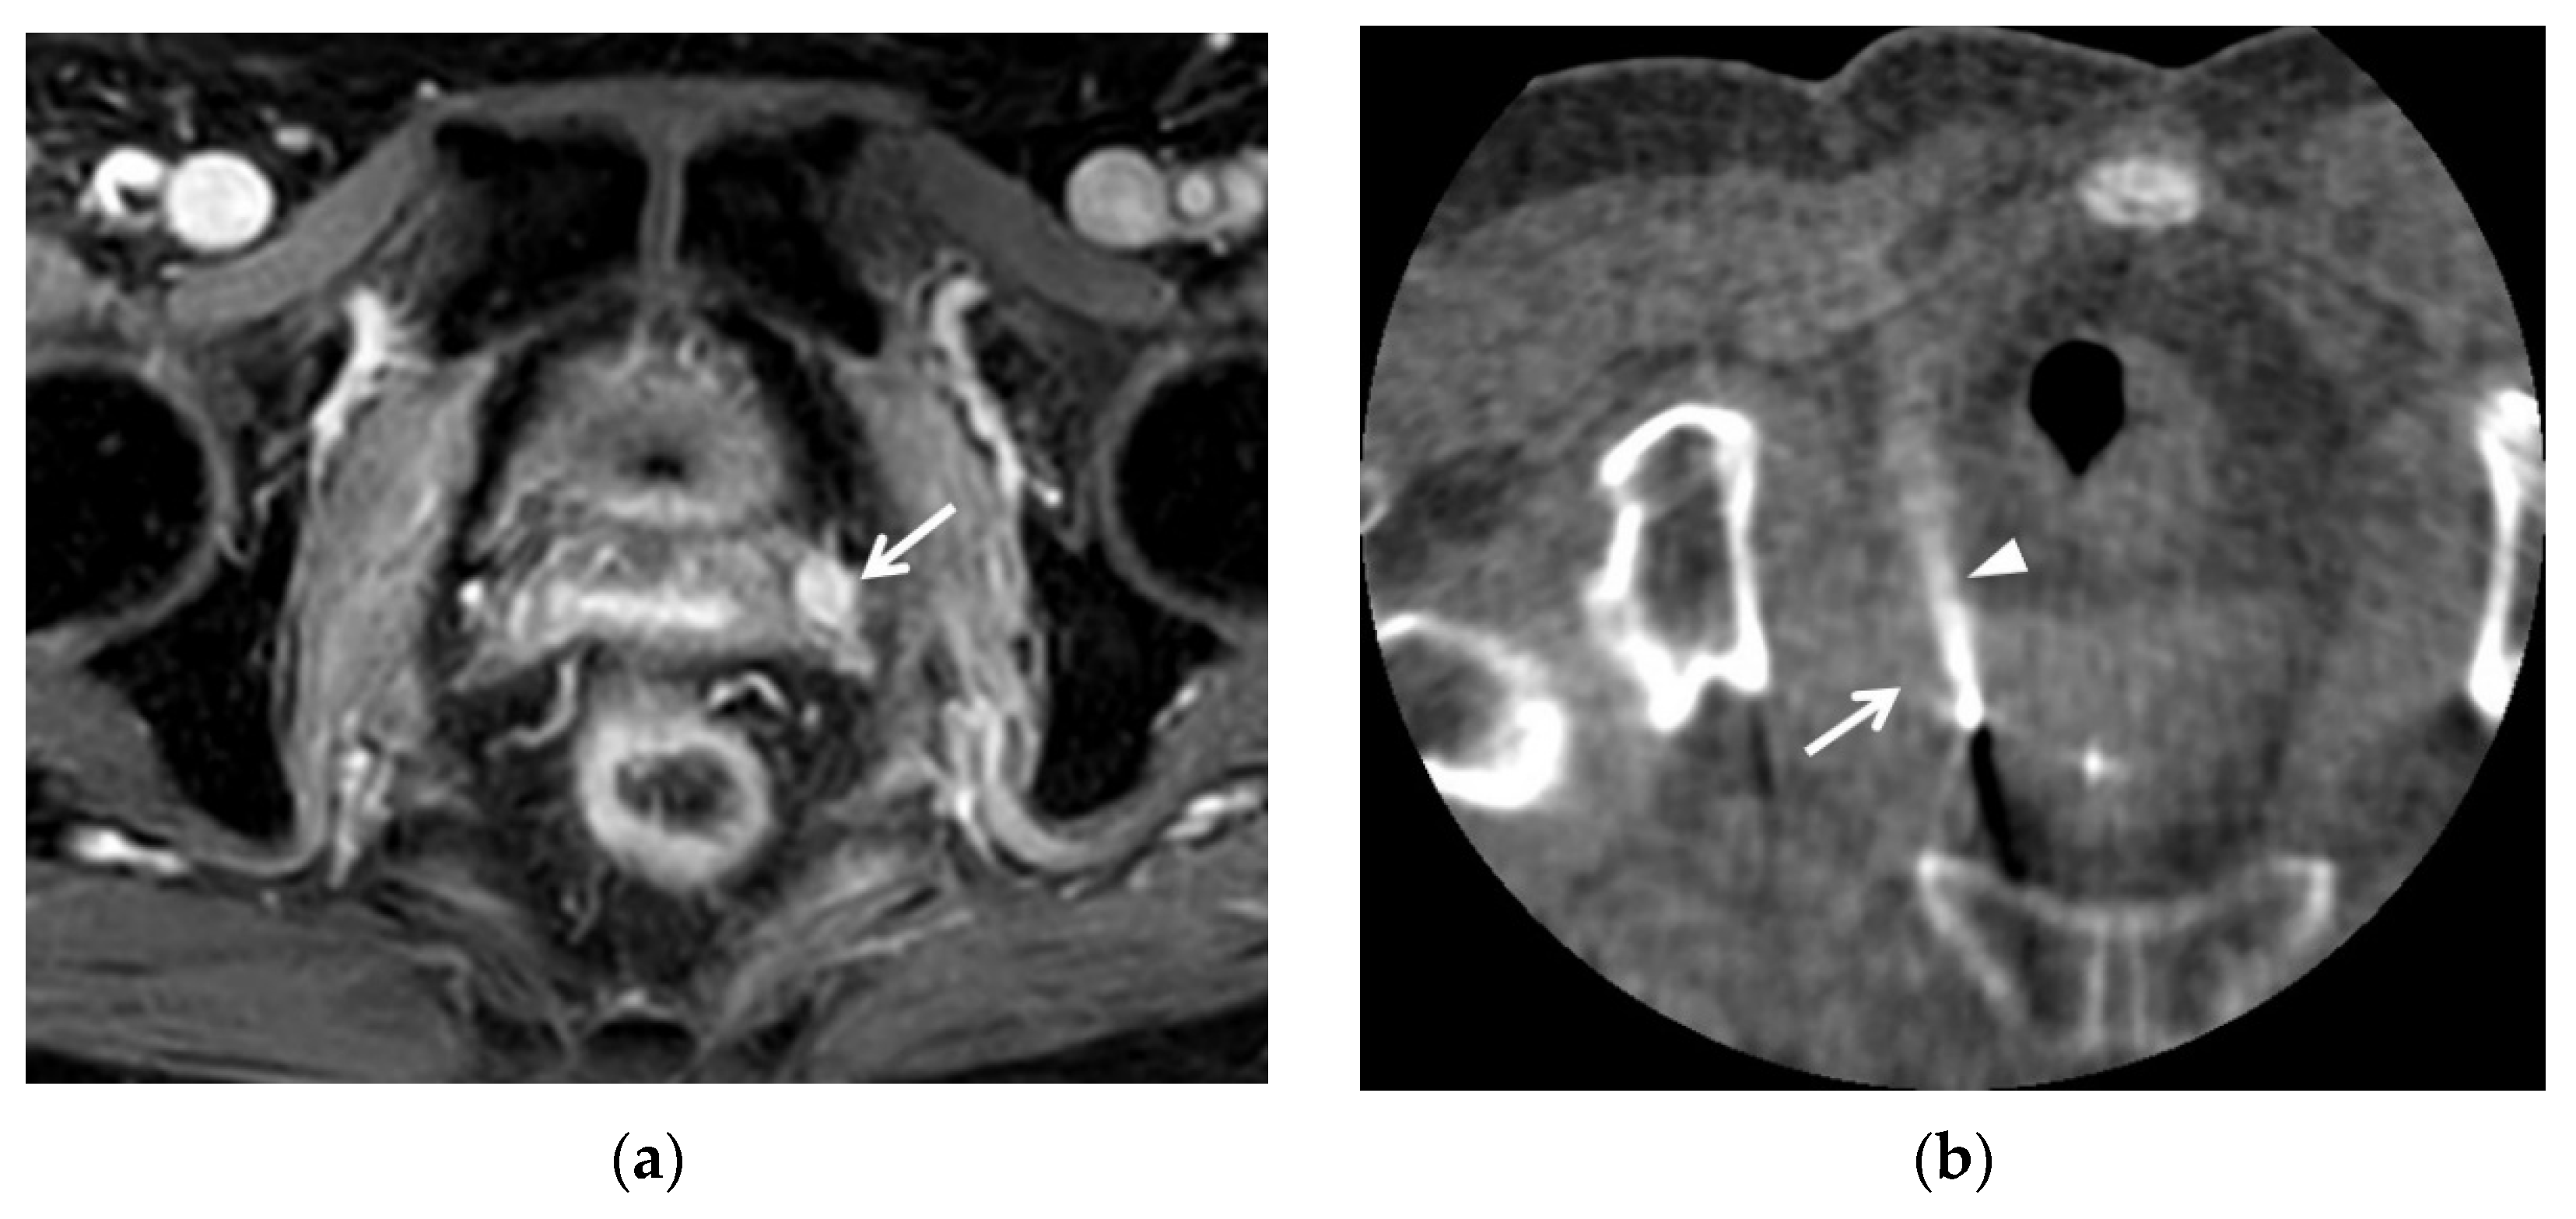

4. Post-Conization MRI

5. Post-Trachelectomy MRI